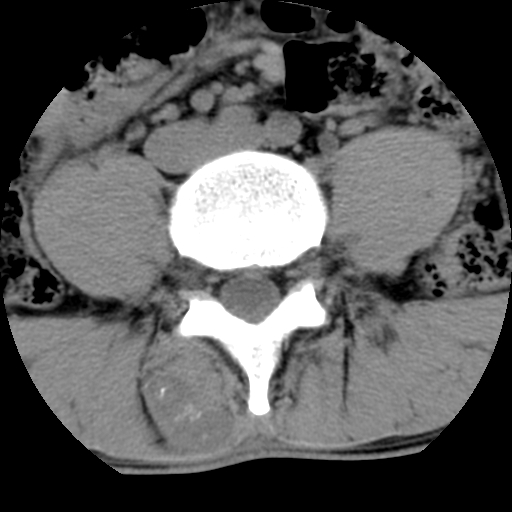

标题: CT16890:男,腰背痛.

男,腰背痛

本人诊断1tb2包虫,请会诊

1)右侧竖脊肌稍低密度肿块伴钙化(性质待定),不排除肿瘤可能;建议行进一步检查。2)腰椎间盘突出。

右侧竖脊肌稍低密度肿块伴钙化(性质待定),

1.右侧竖脊肌软组织肿块伴团块状钙化,首先考虑血管瘤可能性大;建议行进一步检查;2。腰椎间盘突出。